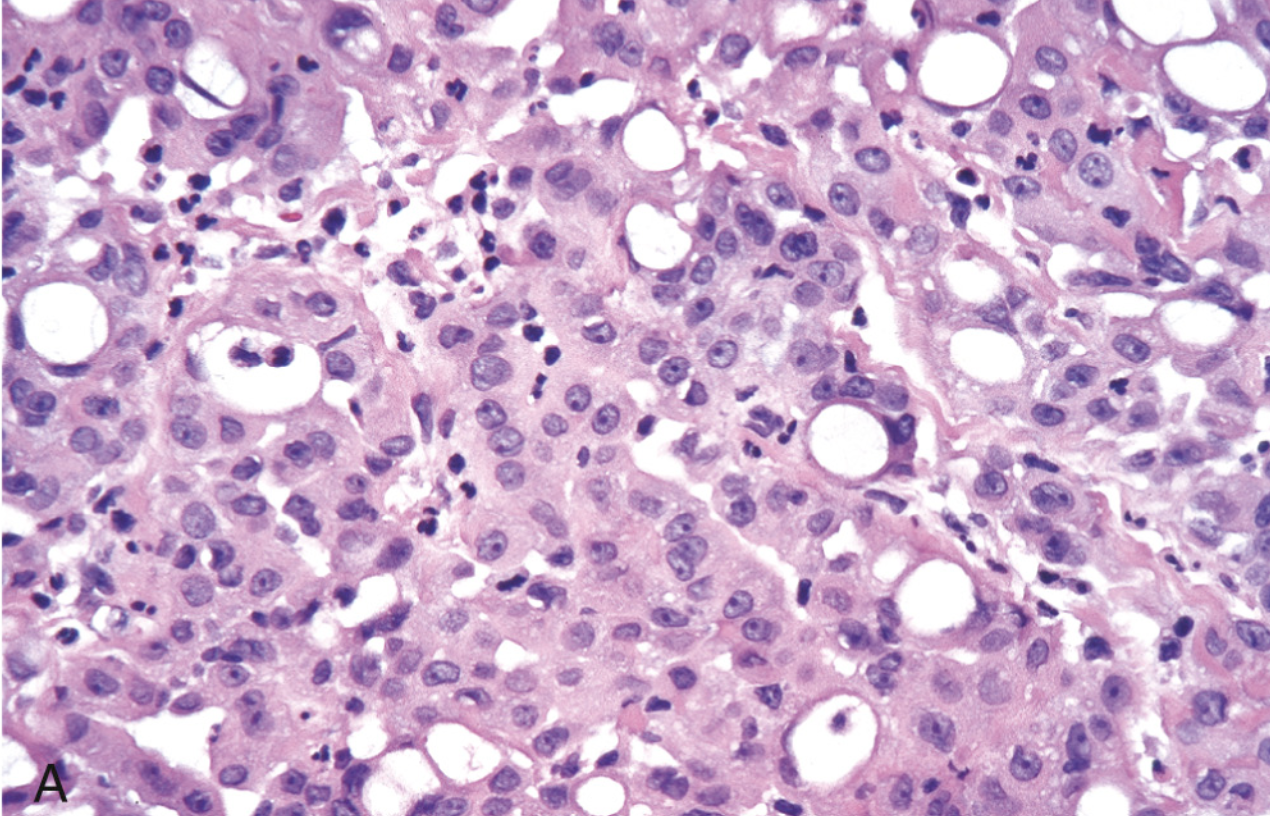

<p>Carcinoma de células gigantes</p>

Carcinoma de células gigantes